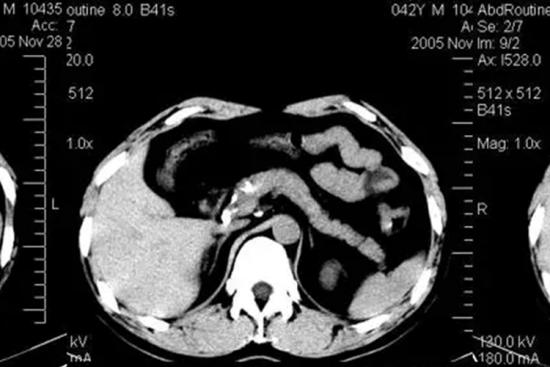

上腹部CT检查通常包括肝脏、胆道系统、胰腺、脾脏及部分肾脏,除此之外,还可以检查到上述脏器邻近的腹腔、肠道、胃等部分区域。

CT是对消化系统、脾和腹膜腔疾病最主要的检查手段,通常上腹部脏器发生问题,可通过CT的检查方法帮助了解脏器病变情况。